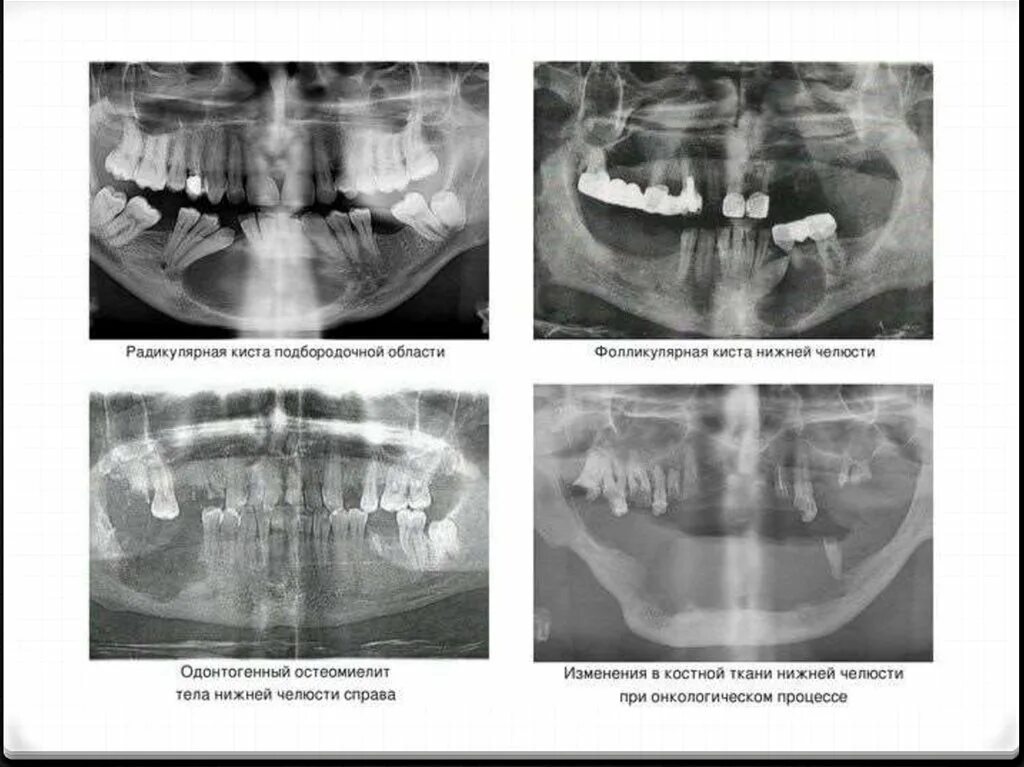

Перелом челюсти код мкб